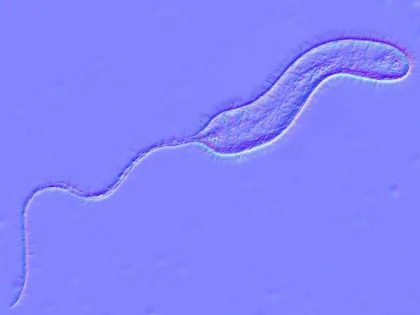

Туристка привезла в Россию из Таиланда холерный вибрион

Фото: Kateryna Kon/Shutterstock/Fotodom В Красноярском крае зарегистрировали первый случай острой кишечной инфекции, вызванной холерным вибрионом.